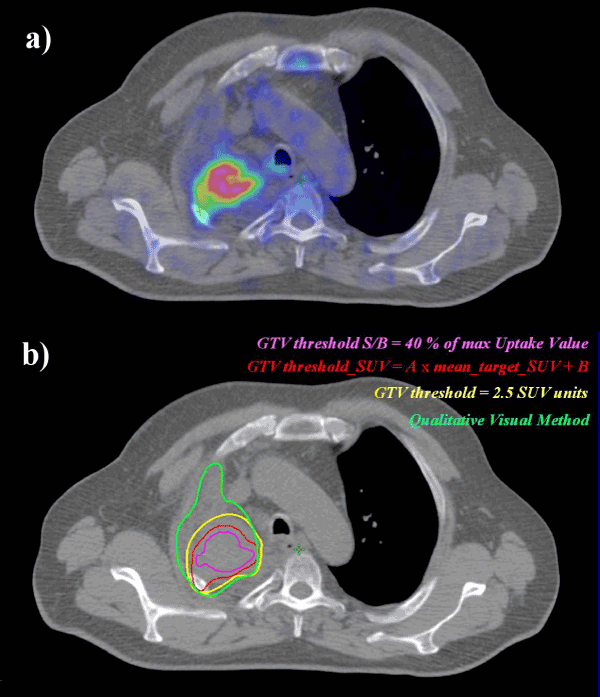

| Figure 1: Various thresholding methods for GTV outlining on a PET image: a) co-registered PET/CT slice image of NSCLC patient; b) various contours following several guidelines for GTV outlining on a PET image superimposed over the corresponding CT slice. |